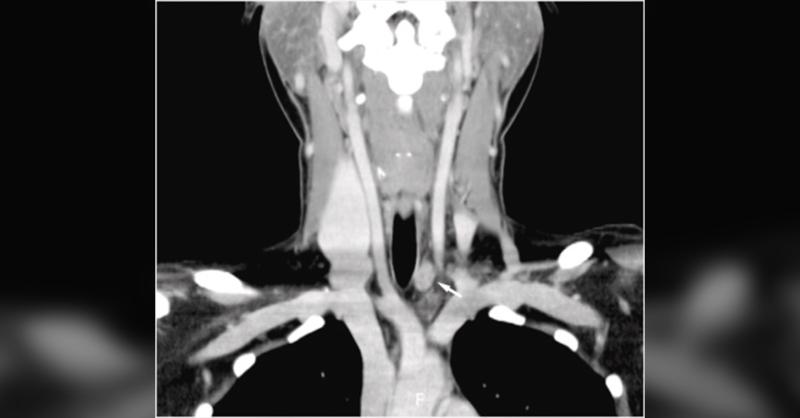

- Coexistence of Left Recurrent and Non-recurrent Laryngeal Nerves in Thyroid Surgery: A Case Report

In thyroid surgery, the recurrent laryngeal nerve (RLN) is an essential part. Asphyxia, hoarseness, and dyspnea could arise from RLN damage (1). Iatrogenic nerve damage during thyroid surgery is frequently caused by anatomic changes in the RLN (1). However, these differences make preoperative USG and CT imaging of the nerve difficult. As a result,